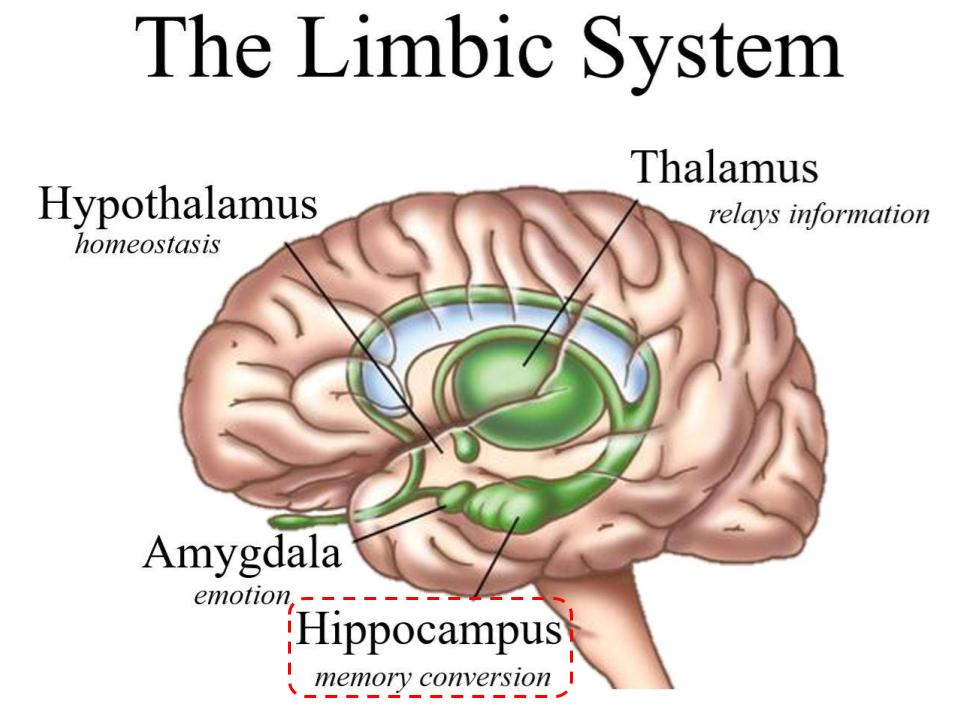

Which Diencephalon structure contains the Pineal Gland(secretes Melatonin)

Epithalamus

Which structure is a switchboard where neurons synapse to get to the precentral gyrus?

Thalamus

Which structure is the master control of the ANS and endocrine system, and regulates body temp/sleep/intake?

Hypothalamus

Which Limbic system structure is vital for memory?

Hippocampus

Which limbic system structure is vital for Emotion?

Amygdala